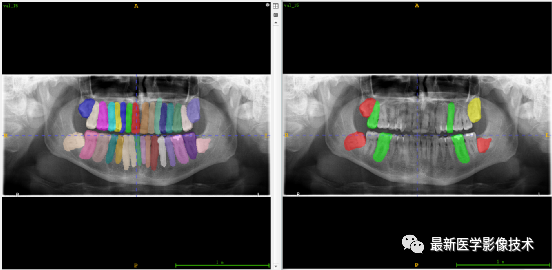

验证集牙齿分割计数和异常牙齿分割识别

左图是分割计数,右图是异常牙齿分割识别结果